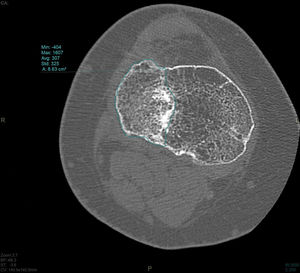

In the CT study, volumetric acquisition was performed using a multi-slice scanner at .6mm thickness, followed by multiplanar reconstruction at 1.5mm slice intervals. In coronal plane reconstruction, the point of greatest fracture depression in millimetres, corresponding to the maximum joint step, and the maximum width/transverse diameter in millimetres were analysed. In the sagittal plane, the maximum anteroposterior joint step diameter in millimetres and the maximum external tibial plateau slope in degrees were measured (Fig. 3). Post-processing in the axial plane involved delimiting the fracture contour and calculating the affected area in cm2, as well as determining the maximum anteroposterior and transverse diameters in mm (Fig. 4).

The mean step measured on CT was 3.6mm (SD: 1.9mm). The mean area measured on CT was 17.57cm2 (SD: 6.1cm2). The mean slope was 12.3 degrees (SD: 5.3 degrees).

| Area (cm2) | 17.57 | 6.1 | 15.16 | 19.99 | 6.32 | 32.43 |